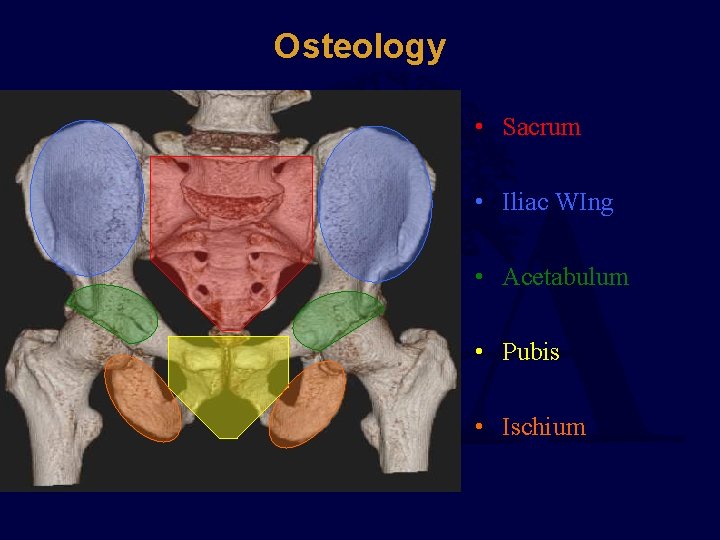

Osteology • Sacrum • Iliac WIng • Acetabulum • Pubis • Ischium